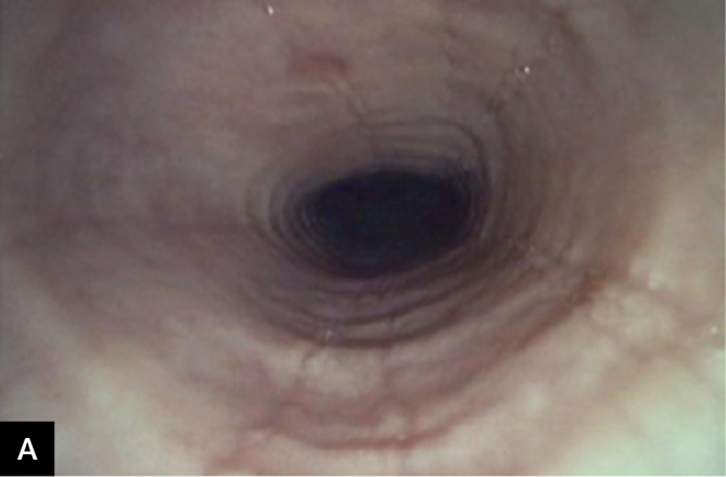

• Colonoscopy